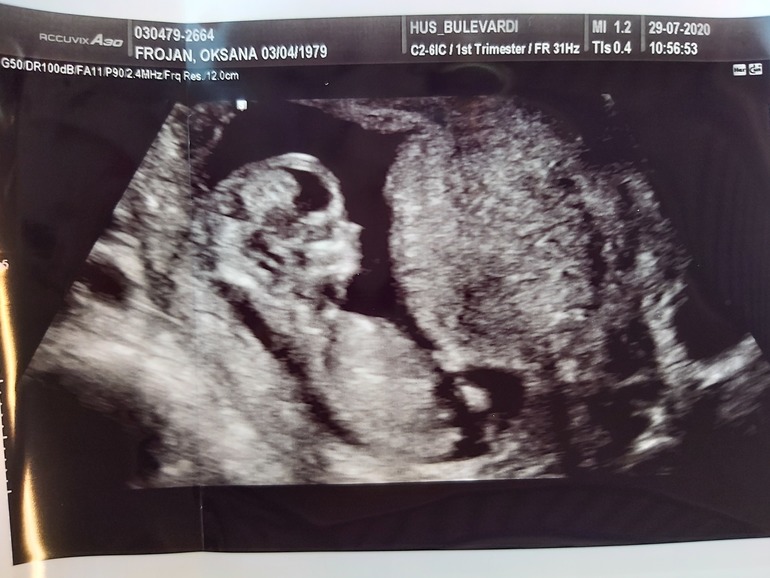

Свершилось! Долгожданный первый скрининг! Наконец-то я услышала,как бьётся сердечко нашего малыша!😍 До сих пор не верится,что внутри меня кто-то живёт 🤣🤭 Анализы все в норме,слава богу,никаких отклонений нет. Сдвинули срок на три дня раньше-по месячным было ровно 12 недель в среду,поставили 12+3. Рост у нас 59 мм,шея 1,2,нос паааапин,армянский видимо будет 🤣🤣. Пыталась разглядеть,кто там ,но ребенок так вертелся, прыгал и скакал,что еле померить удалось))) поэтому пол пока загадка... Сегодня устраиваем ужин и будем сдаваться родителям😁 ...

а может кто сумеет нам пол предсказать по фоткам?;)